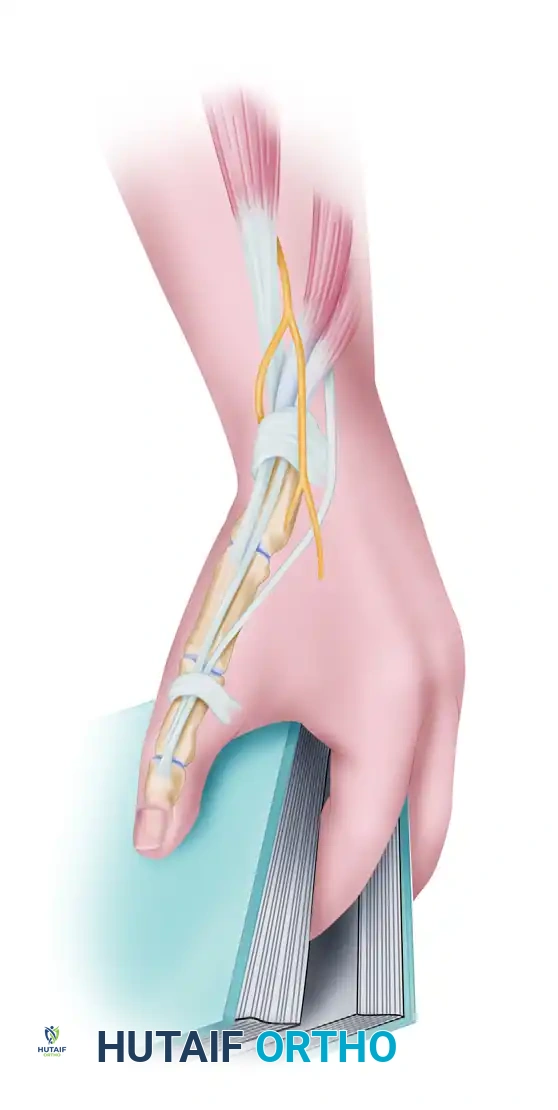

2. Retinacular Incision and Exploration

- Incise the retinacular sheath along its dorsoulnar margin. This specific placement leaves a volar flap of retinaculum to prevent anterior tendon subluxation.

- Explore the sheath and definitively identify both the APL (multiple slips) and the EPB tendon.

Figure: The retinacular sheath is incised. The Extensor pollicis brevis (b) is retracted from the first dorsal compartment. Note the abductor pollicis longus (a).

3. Septum Excision

- If an intracompartmental septum is present, it must be completely excised to ensure full decompression of the EPB.

Figure: Excision of the intracompartmental septum separating the APL and EPB tendons.

4. Retinacular Repair

- To prevent tendon subluxation while maintaining decompression, the retinacular sheath is repaired over the abductor pollicis longus tendon using 5-0 absorbable sutures, effectively creating a widened, reconstructed compartment.

Figure: The retinacular sheath is repaired over the abductor pollicis longus tendon with 5-0 absorbable sutures. The wrist is subsequently immobilized in a splint for 2 weeks.